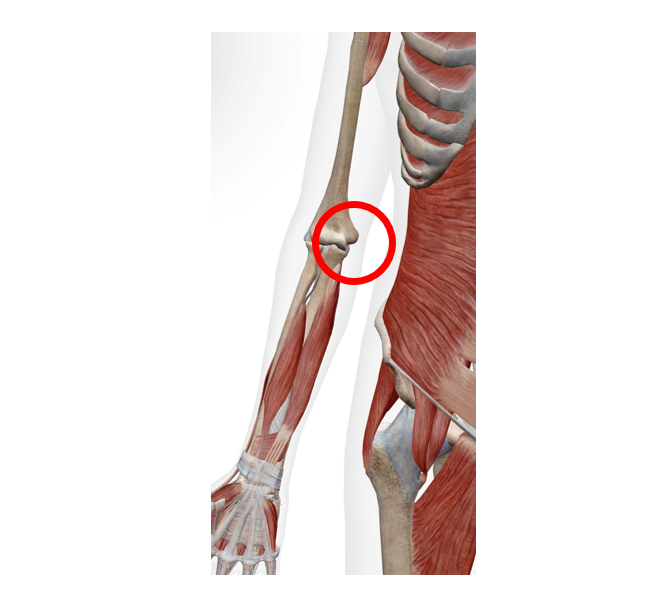

細かく診ていきましょう!ここ!肘がボコっとしているところがわかりますでしょうか。筋肉がここについているため、このボコっとしているところが痛むでしょうか?

尺骨神経の刺激(肘部管症候群)

肘をぐっと(約90°以上)曲げないようにしましょう。肘は曲げると関節への圧力が3倍以上かかるとされています。